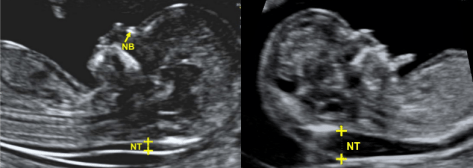

При ультразвуковому скринінговому дослідженні у I триместрі ведеться пошук ультразвукових маркерів хромосомної патології: вимірюється товщина комірцевого простору (Nuchal Nranslucency scan), оцінюється наявність носової кістки, кровоплин в венозній протоці та на тристулковому клапані.

При збільшені товщини комірцевого простору (NT), відсутності носової кістки, патологічного кровотоку в венозній протоці, на тристулковому клапані в серці підвищується рівень ризику виникнення генетичних захворювань (в першу чергу синдром Дауна – трисомія 21 пари хромосом). Також проводиться скринінг анатомічних аномалій плода (вроджених вад).